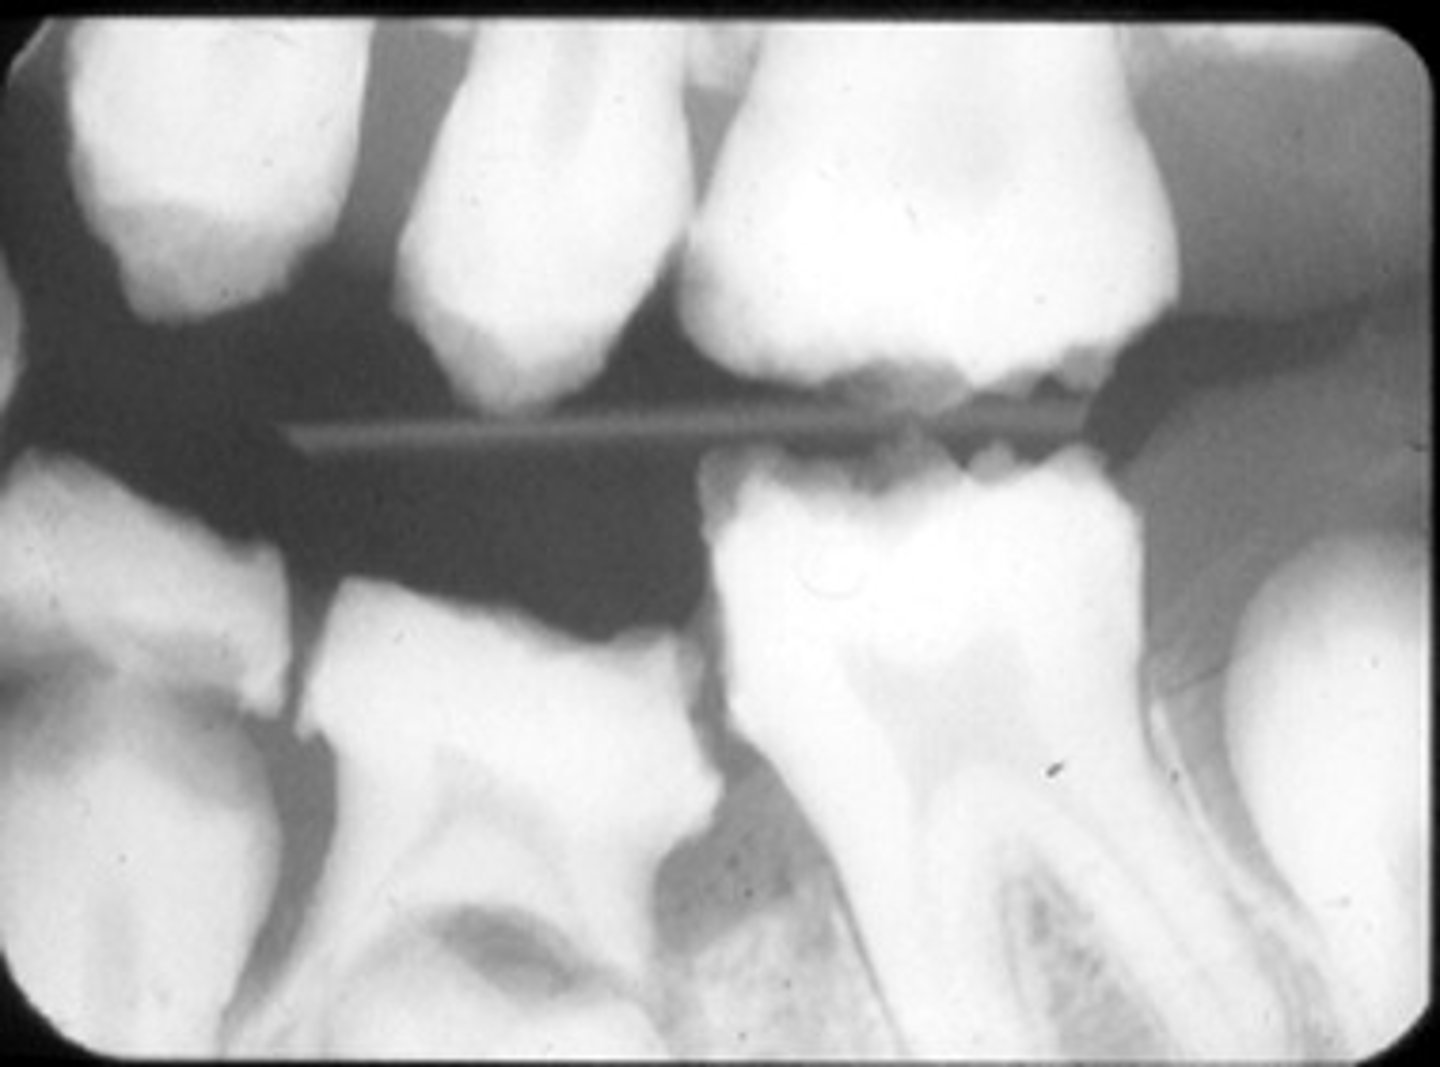

Radiographs with many well-demarcated PARLs. What's next?

- initiate RCT

- endodontic testing

- incision and drainage

- extract

endo testing

- don't perform RCT or ext without confirming diagnosis. Radiographic hard tissue lesions may be benign